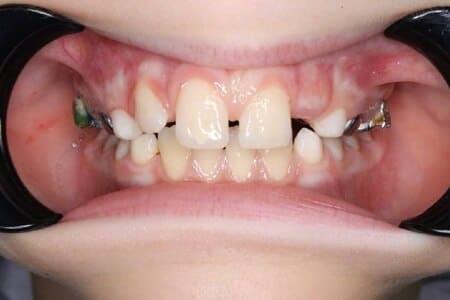

Ласкаво просимо до Центру Дитячої Стоматології Лікаря Ковнацького – місця, де турбота про посмішку вашої дитини стає безтурботною пригодою!

Детальніше...У Центрі Дитячої Стоматології лікаря Ковнацького ми віримо, що візит до стоматолога має бути для дитини не приводом для страху, а кроком до здорової та щасливої посмішки. Наша філософія базується на глибокому розумінні дитячої психології та фізіології, адже дитячі зуби потребують особливого підходу, а малюки – щирої турботи та довіри.